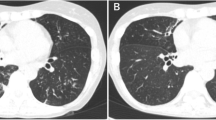

In 2016, the patient initially developed a progressive productive cough and shortness of breath and was diagnosed with emphysema and pulmonary fibrosis. In 2017, while visiting China, he was hospitalized for 10 days and diagnosed with tuberculosis, (though methods of diagnosis were not known to the patient, or available in the medical record) and was subsequently treated with five unidentified oral medications for 6 months. Subsequently, the patient had continued stable shortness of breath on exertion, necessitating three liters of home oxygen. He was started on Nintedanib in 2018, and in 2020 chest computed tomography (CT) imaging demonstrated progressive changes with a right upper cavitary lesion that was retrospectively determined to have originated in 2018 (Fig. 1). In spring 2021, he was referred for an outpatient lung transplant evaluation. Of note, an Interferon-Gamma Release Assay (IRGA) was performed during this evaluation, prior to the current admission, and resulted as positive.

Patients with underlying lung diseases have a higher incidence of NTM infection. Studies conducted in Asia have demonstrated that 35–37% of NTM patients had a prior history of tuberculosis [10, 21]. It is often uncertain whether the NTM infection is a superimposed secondary infection or was present from prior colonization. The patient we reported here is a Chinese immigrant who had a history of chronic pulmonary fibrosis and emphysema diagnosed in 2016 and pulmonary tuberculosis diagnosed in 2017 during a trip in China. He completed a course of anti-tuberculous therapy upon return to the United States with documented clearance of sputum AFB cultures. However, a thoracic CT chest in 2020 demonstrated progressive changes with a right upper cavitary lesion reported since 2018. The upper lobe cavitary lesions were initially considered bullous changes attributed to his underlying pulmonary fibrosis. However, the subsequent diagnosis of M. kumamotonensis infection as described in this case raises the possibility that this organism may have contributed to the progression of his lung disease. Furthermore, administration of steroids without anti-mycobacterial coverage may have contributed to accelerated disease progression. The laboratory workup of TB in 2017 is also unknown, and it is therefore possible that M. kumamotonensis was misidentified as TB or that the patient had co-infection with TB and M. kumamotonensis at that time. M. kumamotonensis may be resistant to some agents included in standard anti-tuberculous therapy (such as rifampin) and inadequate treatment may cause relapse over time [14]. A new superimposed M. kumamotonensis infection is also possible, but given the progressive clinical and radiographic changes following TB and the geographic distribution of M. kumamotonensis, the findings suggest that this organism had contributed to progressive pulmonary infection over a longer period of time.